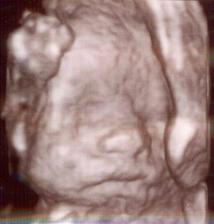

Toto je ten najkrajší zázrak na svete 🙂)) Dňa 10.6. 2009 potvrdená akcia srdiečka nášho bubáčika a rastieme ako z vody - máme 12,6 mm. Už teraz sa tešíme na prvú poradňu ktorá bude 1.7. na ktorej nám dajú vytúženú tehu knižočku a obrázok nášho zázraku 🙂)) Dňa 20.9. sme boli na 3D ultrazvuku, kde nám pán doktor povedal, že čakáme chlapčeka 🙂)) Tak sa z neho veľmi tešíme 🙂))